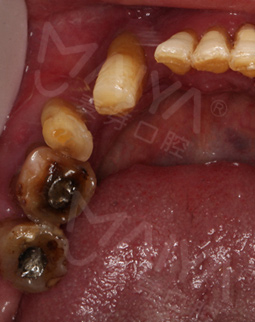

麦芽的博士专家团在看过我的片子后发现,我的牙齿由于长期对口腔疏于护理,牙周情况非常差,余牙有些松动,且牙槽骨萎缩严重,现存的骨量无法进行传统的种植牙手术,因此给我设计了“all-on-4”种牙技术的升级版本“all-on-5”,前期是要处理我的牙周问题,当天就给安排了洁牙,然后上药,等牙周恢复差不多就可以进行种植了!

经过一个月的牙周治疗,牙齿肿胀部分都已经消退,来麦芽种牙之前,心理还有点小紧张,总害怕种牙特别疼,恢复时间慢。我的牙齿情况比较复杂,部分牙齿有牙槽骨吸收,经过前期的各种检查,医生说我的身体状况适合种牙。